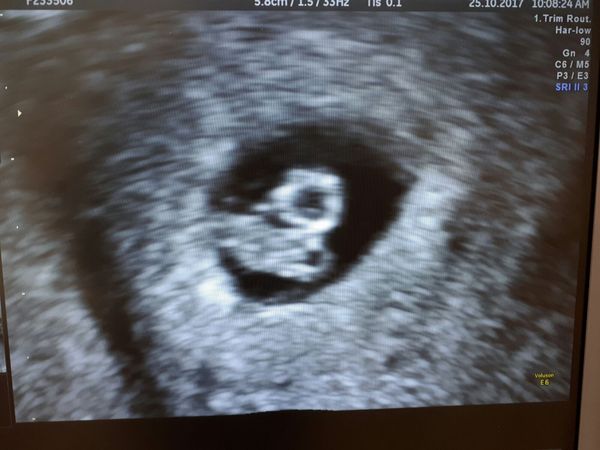

Mummyloves09 · 25/10/2017 12:42

Hey ladies,

So today has been a good day little bean is all good with a 156bpm, and the measurements have triple in the last 14 day so it's growing nicely.

I had a senior consultant today who said the bleeding/spotting was ok as long as it isn't Heavy bleeding.

They corrected our date so baby is now due on 11/6/18.